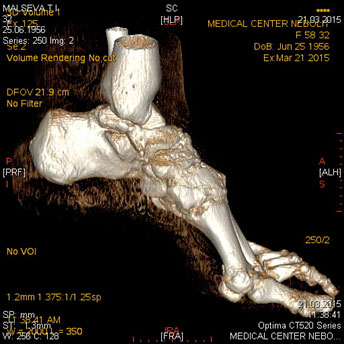

Компьютерная томография костей и суставов

Показания:

- подозрение на опухоль, метастатическое поражение

- воспалительные поражения (специфические, неспецифические)

- дегенеративно- дистрофические процессы

- врожденные аномалии развития